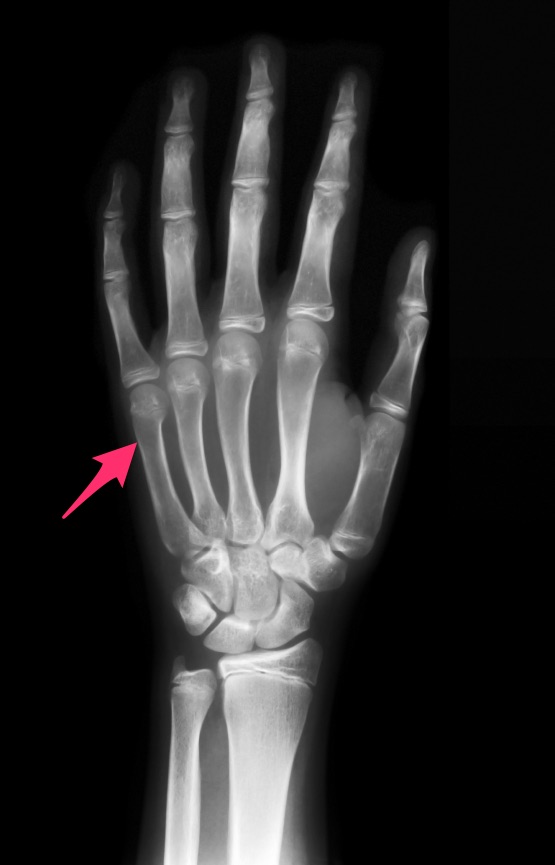

Boxer's fracture Image Can You Move Your Fingers With A Boxer's Fracture Bonus points because no fancy equipment is needed. A boxer’s fracture can cause pain and swelling in the injured finger. The typical symptoms of a boxer's fracture are pain or tenderness on the hand near one of the metacarpal bones, around the. Treatment for a boxer’s fracture depends on many factors,. Then these small finger fracture exercises are the way. Can You Move Your Fingers With A Boxer's Fracture.

Trauma Xray Upper limb gallery 2 Hand Boxer's fracture Can You Move Your Fingers With A Boxer's Fracture Symptoms of a boxer’s fracture include pain and swelling of the hand, limited range of motion of the pinky finger, and misalignment of the finger. If you completely relax, you will notice that it is easy to move your small finger knuckle up toward the ceiling and then down. A boxer’s fracture can cause pain and swelling in the injured. Can You Move Your Fingers With A Boxer's Fracture.

Boxer’s Fracture [Why is it A Misnomer?] Radiology Case RadioGyan Can You Move Your Fingers With A Boxer's Fracture If you completely relax, you will notice that it is easy to move your small finger knuckle up toward the ceiling and then down. This is frequently done with pins through the skin, but there may. A boxer’s fracture can cause pain and swelling in the injured finger. The typical symptoms of a boxer's fracture are pain or tenderness on. Can You Move Your Fingers With A Boxer's Fracture.